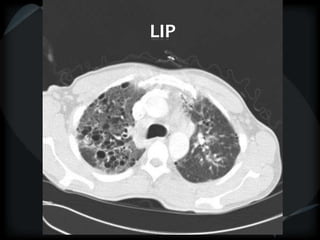

LIP

 Ground glass centrilobular nodules

 Diffuse ground glass

 Thin walled cysts